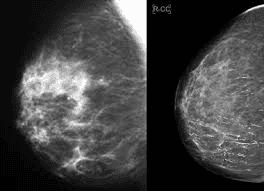

3.1. Chụp nhũ ảnh

Chụp nhũ ảnh về bản chất là thực hiện chụp X-quang tuyến vú. Chụp nhũ ảnh là cách tốt nhất để phát hiện sớm ung thư vú, trước khi ung thư biểu hiện các dấu hiệu hoặc triệu chứng, nhằm điều trị dễ dàng hơn, đạt kết quả tốt hơn.

Chụp nhũ ảnh với tần suất hợp lý có khả năng hạ thấp nguy cơ tử vong do ung thư vú, và cho đến hiện nay, đây là phương pháp phát hiện ung thư vú tốt nhất đối với đa số phụ nữ.

Tuy nhiên chụp nhũ ảnh không phải là không có những hạn chế nhất định, đối với những phụ nữ có mô vú đặc, việc phát hiện ung thư trên kết quả chụp nhũ ảnh sẽ khó khăn.

Chụp nhũ ảnh đang là phương pháp tầm soát ung thư vú tốt nhất